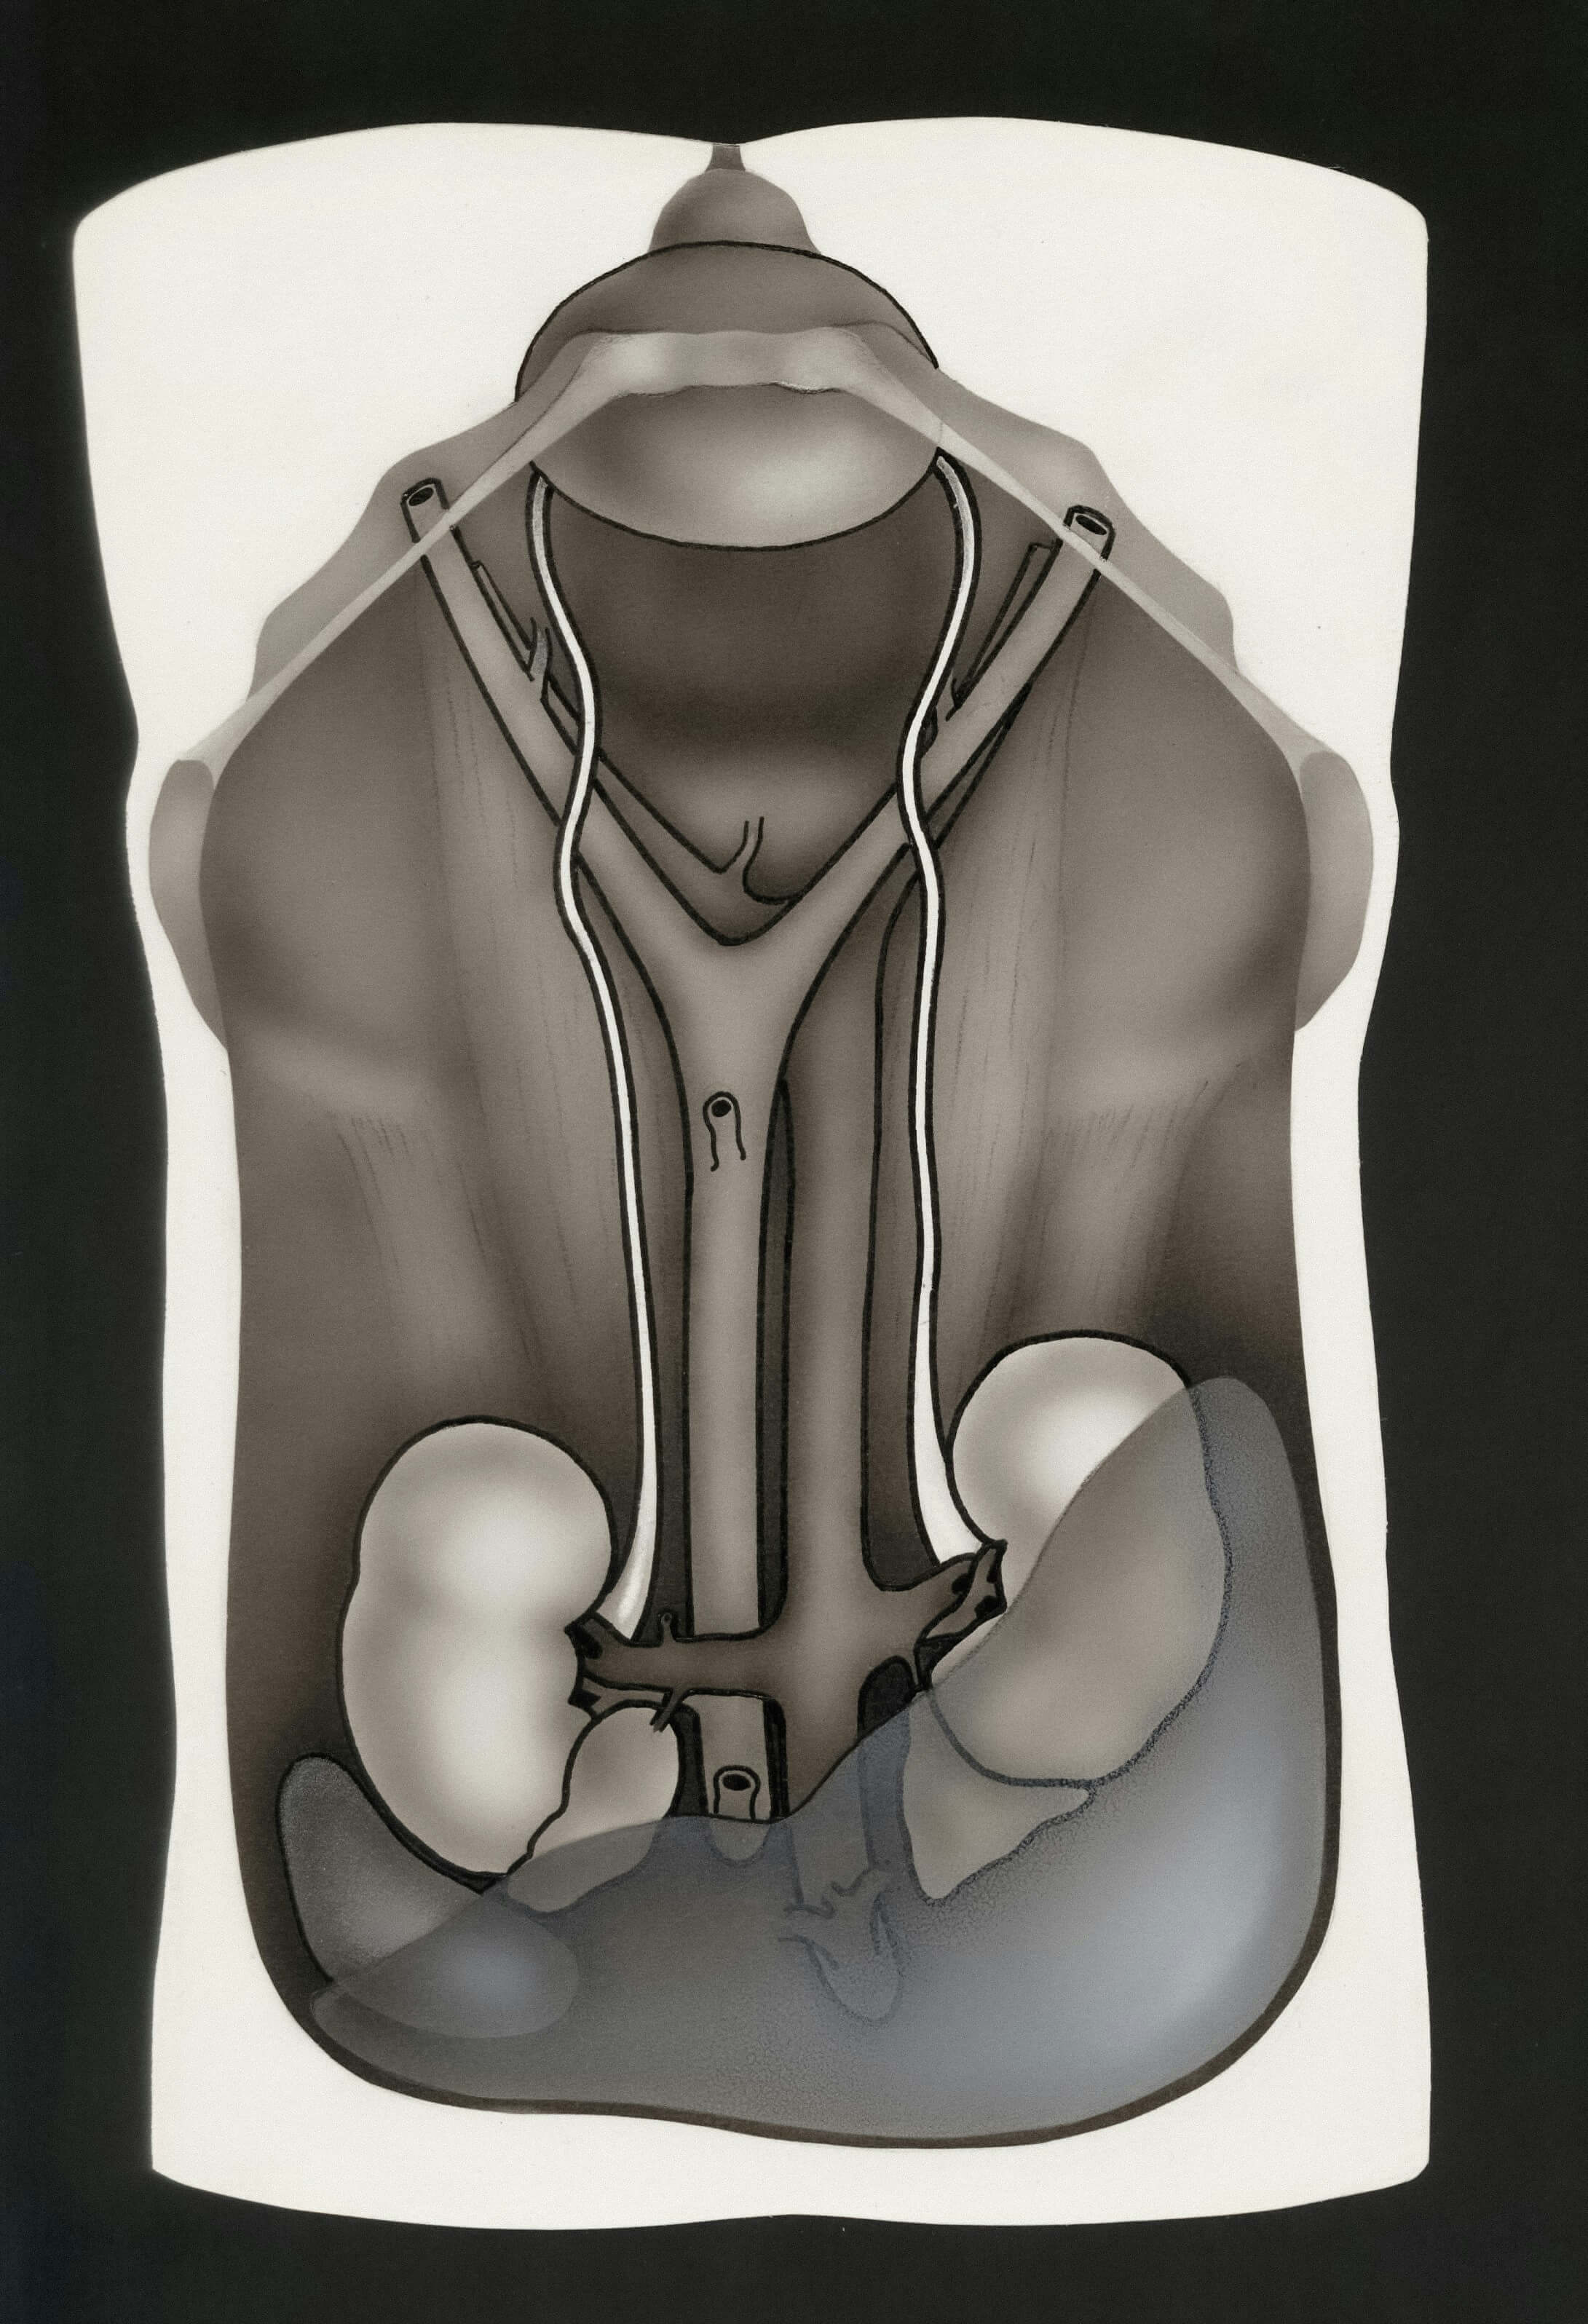

흉관 삽입술 (중등도-중증)

대상: 기흉량이 많거나 증상이 심한 경우

- 국소마취 후 가슴에 튜브 삽입

- 늑막강의 공기 제거

- 입원 치료 필요 (3-7일)